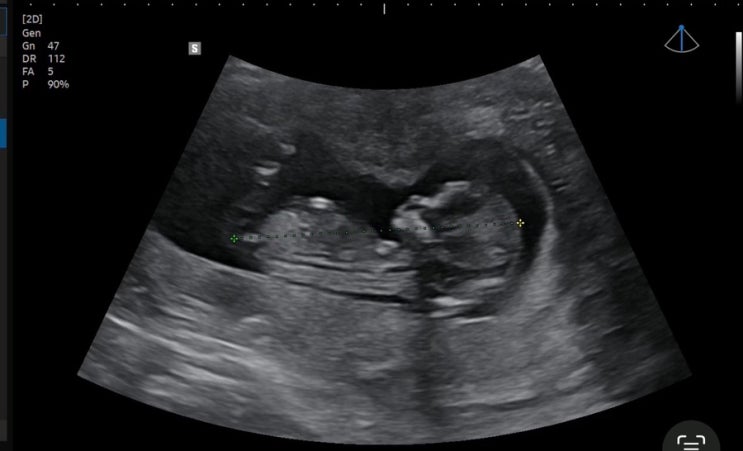

[임신 6주차] 증상, 본격 입덧 과정, 첫 심장소리❤️